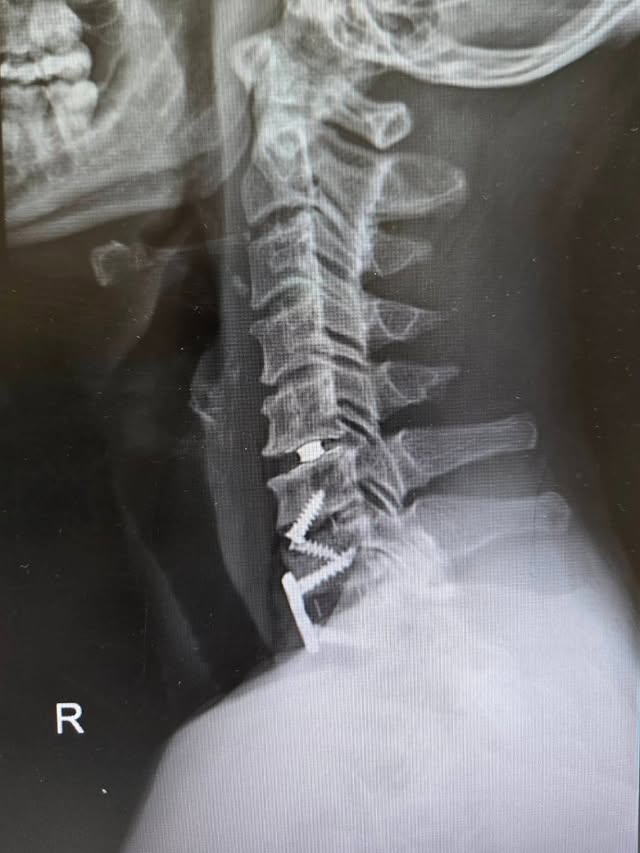

กลับไปพักฟื้นร่างกายที่บ้านเป็นที่เรียบร้อยแล้ว สำหรับนักร้องร็อกเกอร์ขวัญใจมหาชน ตูน บอดี้สแลม หลังเข้ารับการผ่าตัดเมื่อวันที่ 22 มกราคม 2569 จากอาการภาวะกระดูกสันหลังส่วนคอเสื่อมและกระดูกงอก ซึ่งมีการกดทับเส้นประสาทแขนซ้าย ส่งผลให้เจ้าตัวต้องประกาศพักงานชั่วคราวเป็นเวลา 30 วัน เพื่อฟื้นฟูร่างกายอย่างเต็มที่

ล่าสุด ตูน ได้ออกมาอัปเดตอาการผ่านอินสตาแกรมส่วนตัว ด้วยการโพสต์ภาพฟิล์มเอกซเรย์หลังการผ่าตัด พร้อมแคปชันให้กำลังใจตัวเองและแฟน ๆ ว่า

“No Regrets🧡 VERSION 47th UPGRADED✨️🔩🩻 รัก🌈 #ArtiwaraHimselfDiary #ใช้ชีวิตให้สนุกครับ”